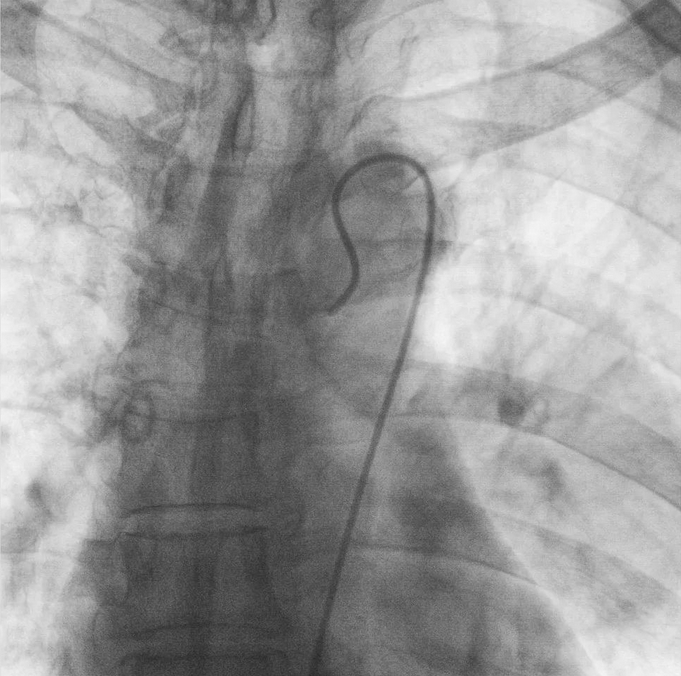

在普愛醫(yī)療移動式平板介入中C影像的引導下,醫(yī)生為患者實施雙側(cè)支氣管動脈栓塞+化療灌注術(shù)。

在微導絲的配合下,先后分別超選擇①至3支左側(cè)支氣管動脈腫瘤供血動脈,經(jīng)微導管推注栓塞微粒球栓塞腫瘤動脈。栓塞結(jié)束后,再次用移動式平板介入中C做造影檢查,見腫瘤染色消失。